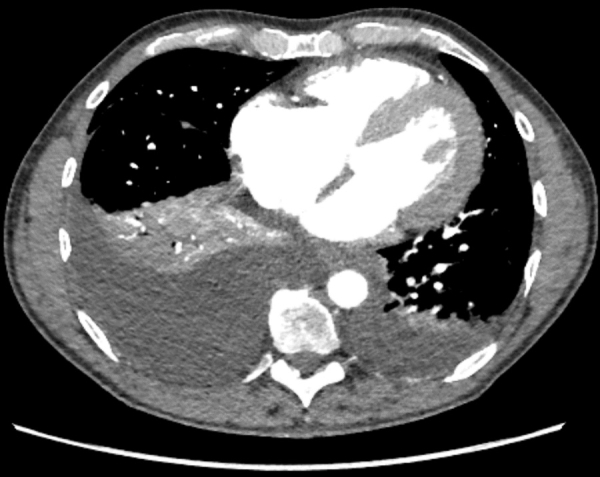

Scanner thoracique injecté en ville pour bilan de dyspnée : mise en évidence d’une cardiomégalie, d’une HVG et des épanchements pleuraux bilatéraux (Figure1).

Figure 1 : scanner thoracique